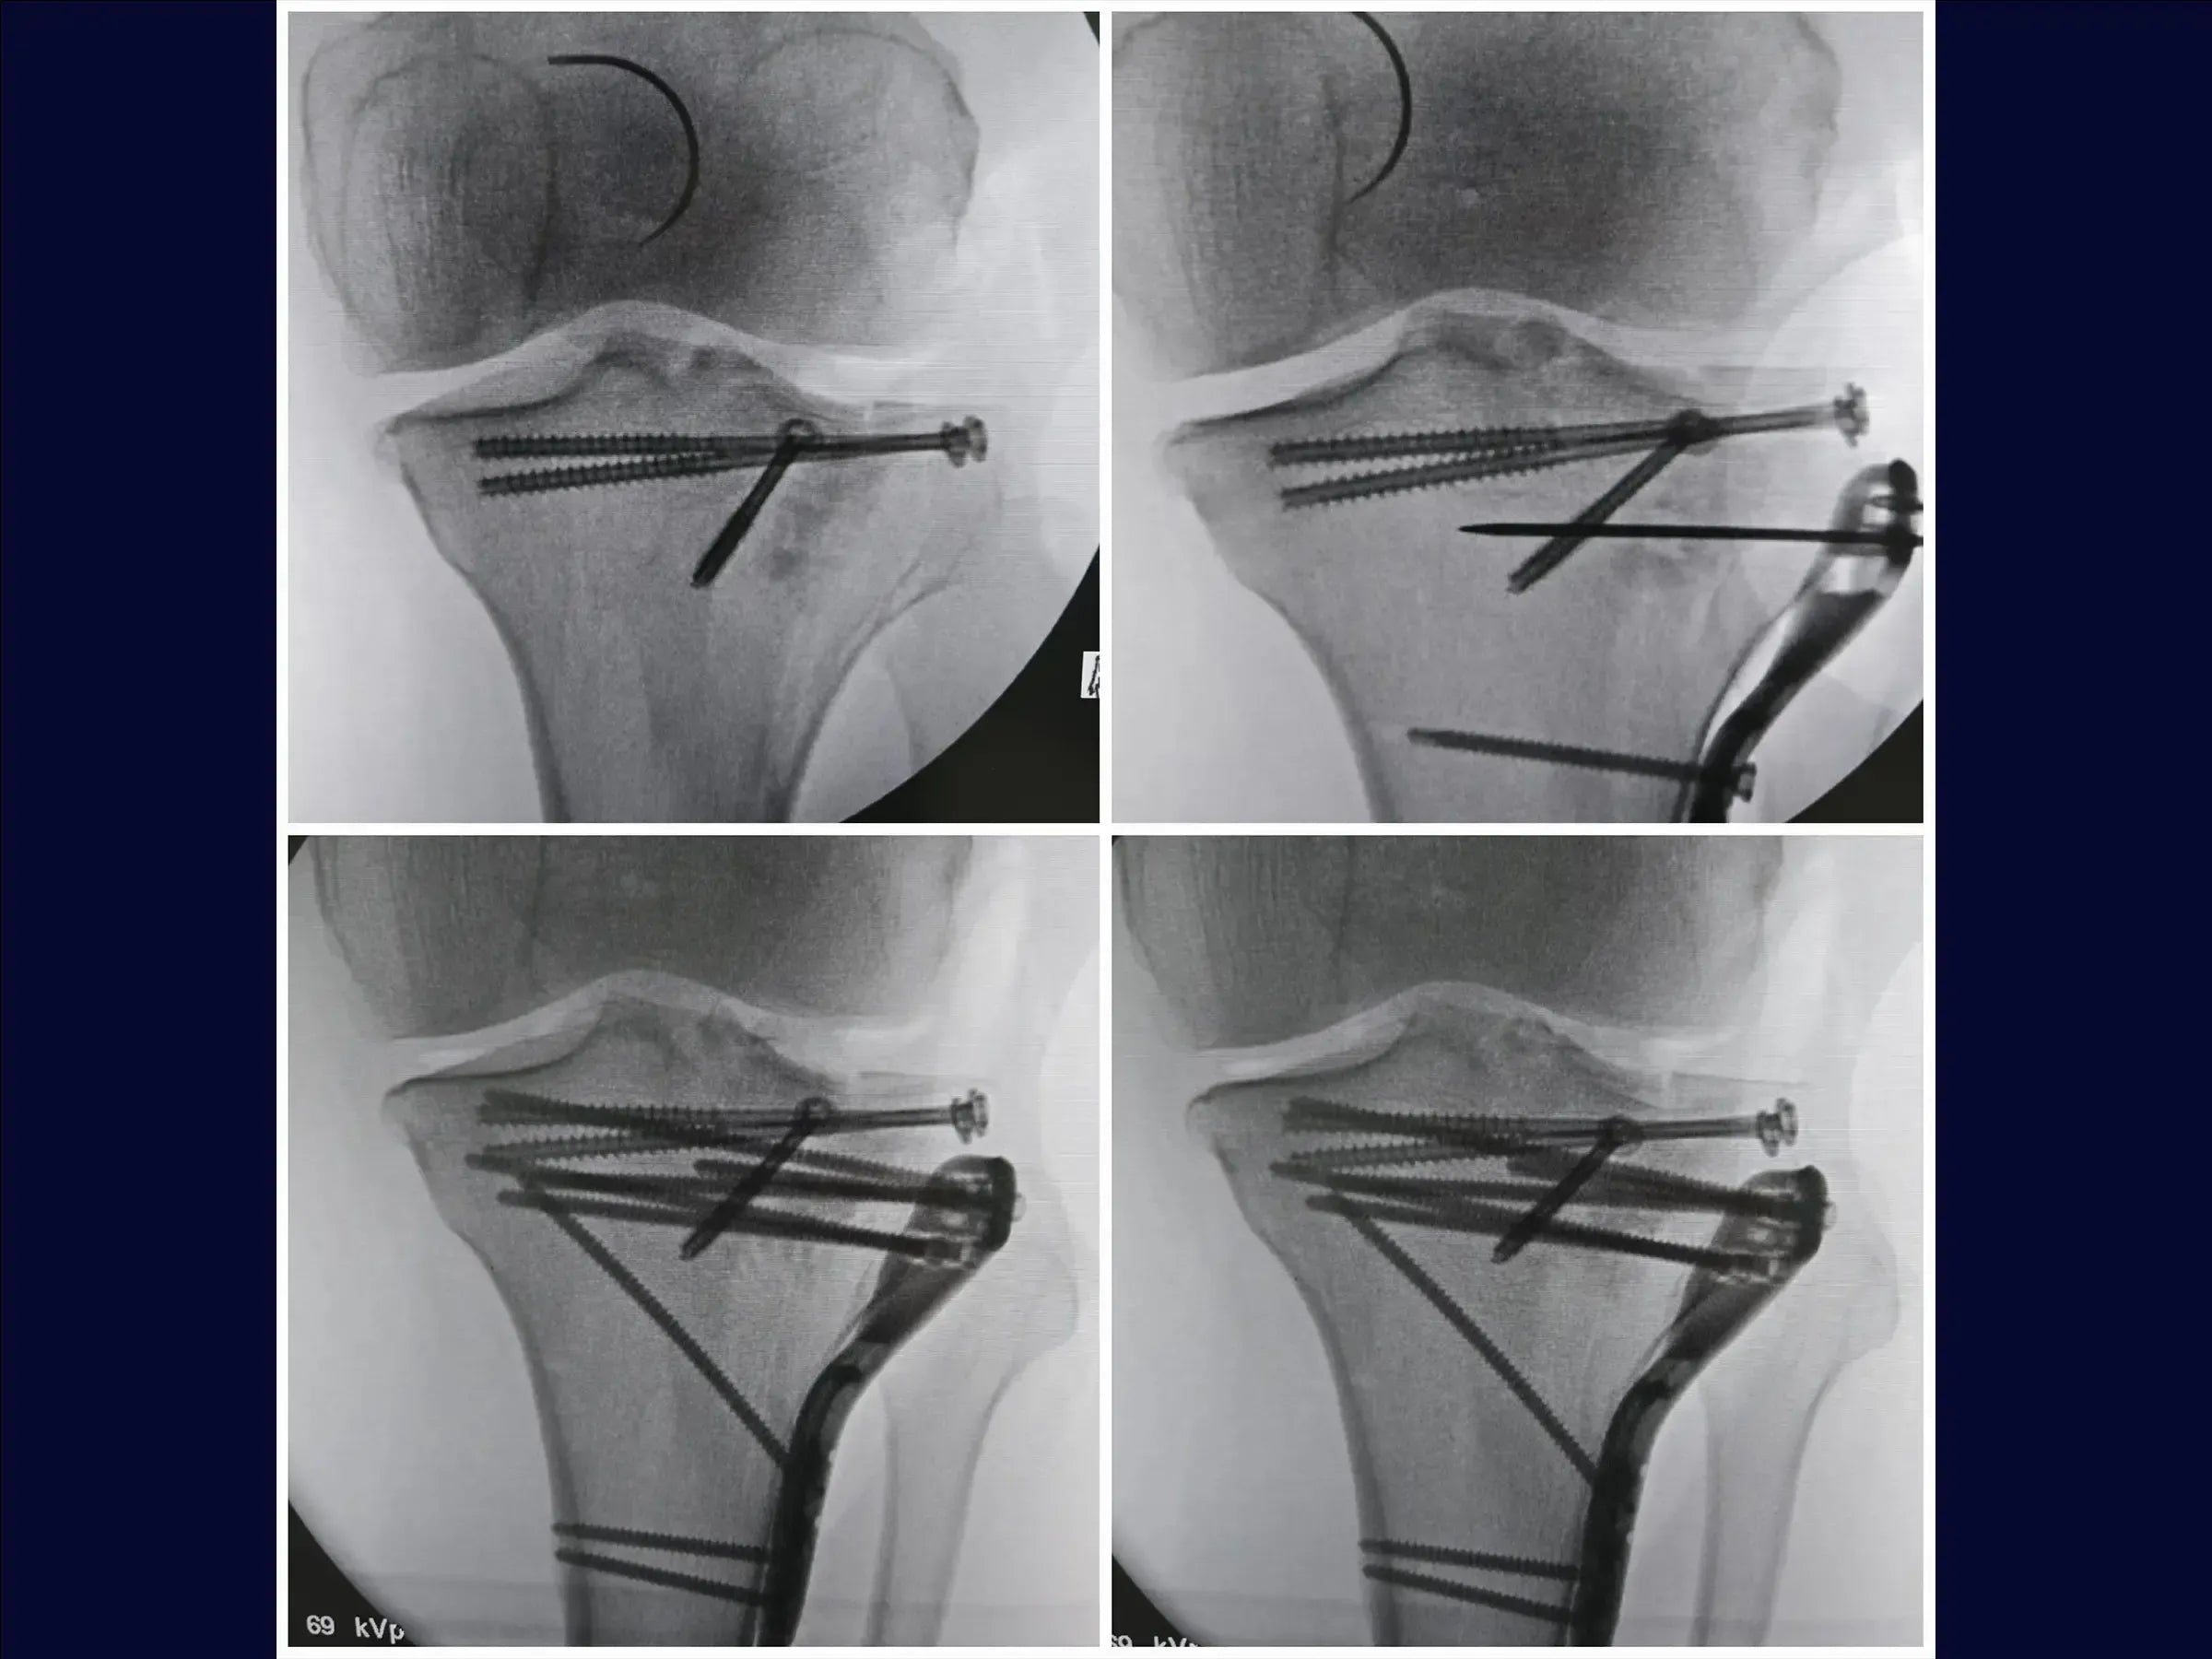

- Osteossíntese de fraturas do platô tibial com afundamento central e cisalhamento incompleto.

- Técnica de osteotomia incompleta (elástica) para levantamento de fragmentos afundados.

- Utilização de enxerto ósseo estrutural e fixação com parafusos canulados subcondrais e placa.

- Osteotomia Elástica para Redução Anatômica: Abordagem de osteotomia incompleta que mantém a cortical anterolateral íntegra, permitindo o levantamento do fragmento afundado com retorno natural à posição.

- Fixação Estável e Rede Subcondral: Posicionamento de fios guia para parafusos canulados subcondrais, criando uma "rede" para estabilidade primária, e utilização estratégica da placa para compressão e manutenção do levantamento.